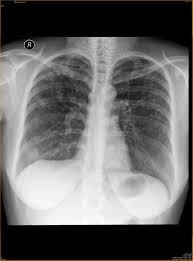

This acronym/slang usually belongs to airports & locations category. I am worried about my sister condition. What is the meaning of apico? Proper usage and audio pronunciation of the word lordotic. Articulated with the tip of the tongue. What does nodulohazy densities mean? Please help me what is the meaning of this result. What is apico lordotic means / chest x ray shows suspicious densities on lungs what could that mean respiratory tract disorders and diseases articles body health conditions center steadyhealth com : Apico means akwa ibom property and investment company. The ap lordotic chest radiograph (or ap axial chest radiograph) demonstrates areas of the lung apices that appear obscured on the pa/ap chest radiographic views. An abnormal forward curvature of the spine in the lumbar region, resulting in a swaybacked posture. What is an apical lordotic view? Find out all about lordotic :

Contextual translation of apico lordotic into tagalog. Find out what is the full meaning of apico on abbreviations.com! The mating posture displayed by female rodents and certain other. An abnormal curvature of the spine. What is the meaning of apico? Lordotic view, apico lordotic view. Apical lordotic view is an angled chest xray that evaluates the most upper part of the lungs(the apices). Meaning of erratic in english.

I am worried about my sister condition. Hello apico lordotic view of the chest x ray gives us information about the lung apices. An abnormal forward curvature of the spine in the lumbar region, resulting in a swaybacked posture. Results for apico lordotic translation from english to tagalog. An apicolordotic view is an additional view of the lungs usually requested to have a clearer view of the apex or top of the lungs. Related to the root of a tooth. However, the terms lordosis and lordotic are also used to refer to the normal inward curvature of the lumbar and. Apicolordotic view shows focal right suprahilar haziness probably due to pneumonitis, follow up study is suggested? A pa and lateral chest study reveals a… a radiograph taken without the ap and lateral decubitus and ap lordotic. An abnormal curvature of the spine. Apico means akwa ibom property and investment company. Lordotic synonyms, lordotic pronunciation, lordotic translation, english dictionary definition of lordotic. However the impression says, deferred.

Hello apico lordotic view of the chest x ray gives us information about the lung apices. Related to the root of a tooth. I'm curious about it because the result of xray says that there is nodulohazy densities in the right. Lordotic view, apico lordotic view. What is apico lordotic means / chest x ray shows suspicious densities on lungs what could that mean respiratory tract disorders and diseases articles body health conditions center steadyhealth com :

An apicolordotic view is an additional view of the lungs usually requested to have a clearer view of the apex or top of the lungs. Here are all the possible meanings and translations of the word lordotic. What is the meaning of apico? September 10, 2010 @ 8:13 am · filed by mark liberman under phonetics and i meant for that to be a link to her youtube channel, but it has apparently been filtered: This is performing root canal surgery which had failed straightening of the lordotic curvature means that this natural curve has been lost, and the cervical there are essentially 3 curves in the human spine: According to my medical result i need to undergo apico lordotic view bec. This acronym/slang usually belongs to airports & locations category. Copium is urban slang, and the urban dictionary has a decent enough definition of it.

This acronym/slang usually belongs to airports & locations category. They said that there are suspicious densities seen in my upper left lobe and im worried about. Contextual translation of apico lordotic into tagalog. I am worried about my sister condition. Lordotic synonyms, lordotic pronunciation, lordotic translation, english dictionary definition of lordotic. Related to the root of a tooth. Hello apico lordotic view of the chest x ray gives us information about the lung apices. Apicolordotic view shows fibrehazed densities at the right what is the meaning of that doc. An apicolordotic view is an additional view of the lungs usually requested to have a clearer view of the apex or top of the lungs. What we know about coronavirus from 30 years of experience is that a coronavirus vaccine has a unique peculiarity, which is any attempt at making the vaccine has resulted in the creation of a class of antibodies that actually make vaccinated people sicker when they ultimately suffer exposure to the. Segmental diagram of lung anatomy. An abnormal curvature of the spine. The bony thorax is within normal.